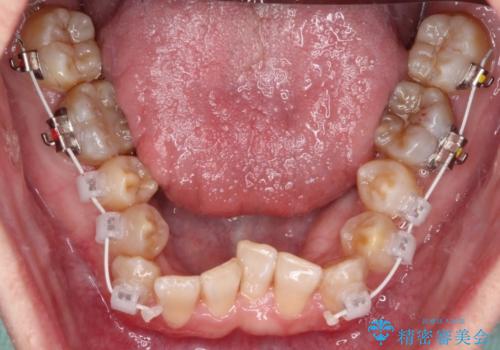

- 矯正装置

- 審美装置

それらを改善するため上顎に拡大装置を用いて、審美装置にてワイヤー矯正を行いました。